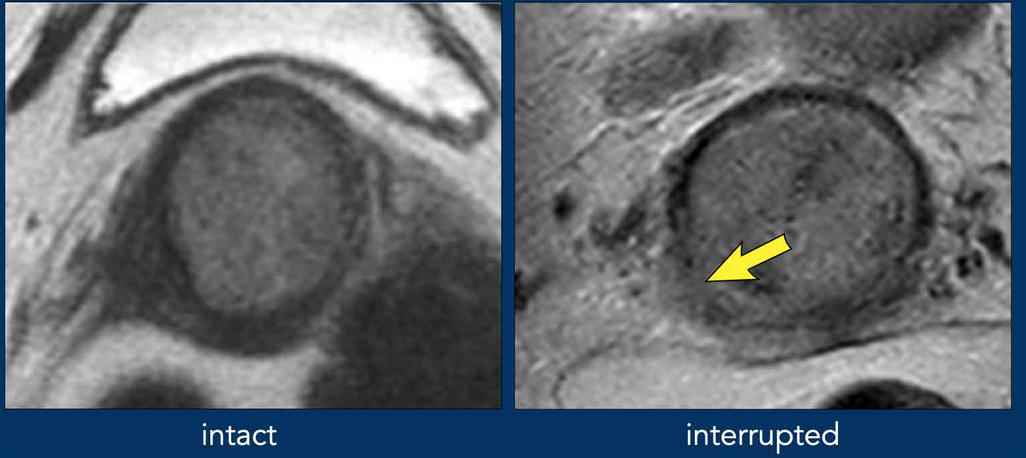

• 2B - Tumor invasion beyond the uterus with para-metrial invasion (basically dark circular border of cervix) - see image —>